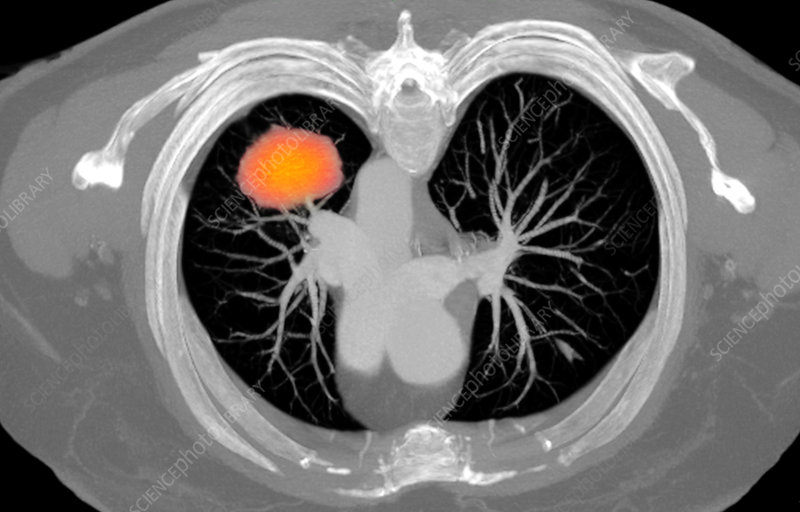

Lung cancer screening is a preventive health measure designed to detect lung cancer before symptoms appear. The gold standard for screening is a low-dose CT scan (LDCT), a specialized imaging test that takes detailed pictures of your lungs using minimal radiation: significantly less than a standard CT scan.

This isn’t your typical X-ray. While chest X-rays can miss early-stage tumors, low-dose CT scans can detect nodules as small as a grain of rice, catching potential cancers when they’re most treatable.